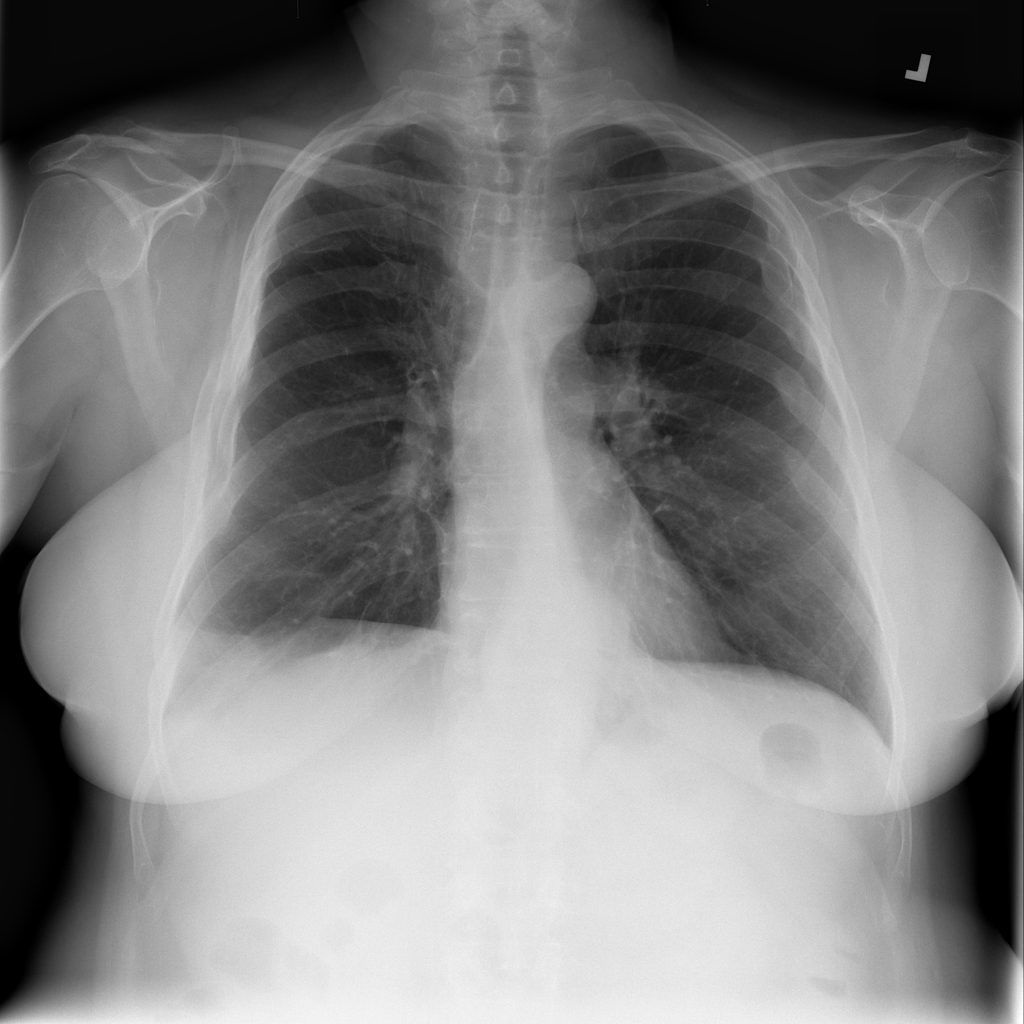

PAT-0ABD · IMG-000Hernia

PAT-0ABD · IMG-000

PA